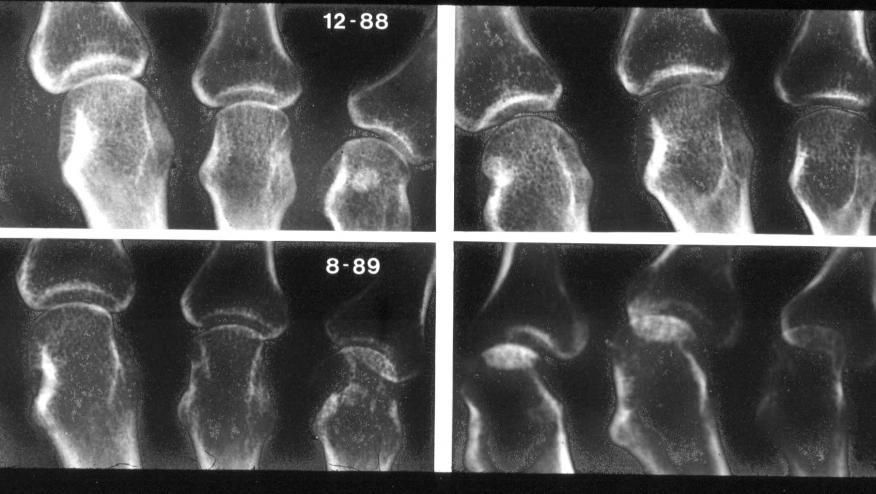

All patients were taking methotrexate or other conventional DMARDs, but previous treatment with biologics was not permitted. Radiographs of the hands and feet were obtained at baseline, 6 months, and 1 year.

Changes in erosion scores from baseline to 1 year were smaller in the two denosumab groups, but there were no differences in joint space narrowing scores.